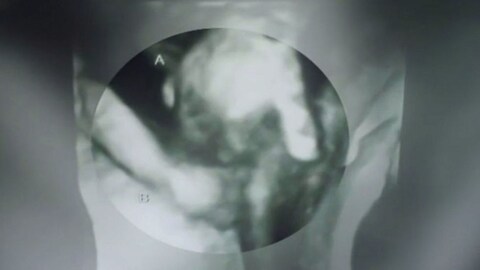

Each subsequent doctor's appointment brought the Hutchinson, Kansas, couple bad news. While the boy, whom the couple named Mason, only weighed 9 ounces, his twin Madilyn weighed 2 pounds. "His only chance of survival would be heart surgery but they wouldn't do heart surgery on him because of his brain," Brittani told KWCH. But they were shocked again when their Tuesday sonogram showed the sick twin's finger holding onto his bigger sister's hand.

There's a chance Mason (pictured above on the left) might not survive the pregnancy, WAAY TV reports, but the sonogram image has given his parents comfort. "[Madilyn's] the only one who can actually be there and holding onto him through it," Brittani told the local news station. "So it's comforting to know that if he does pass, he won't be alone."